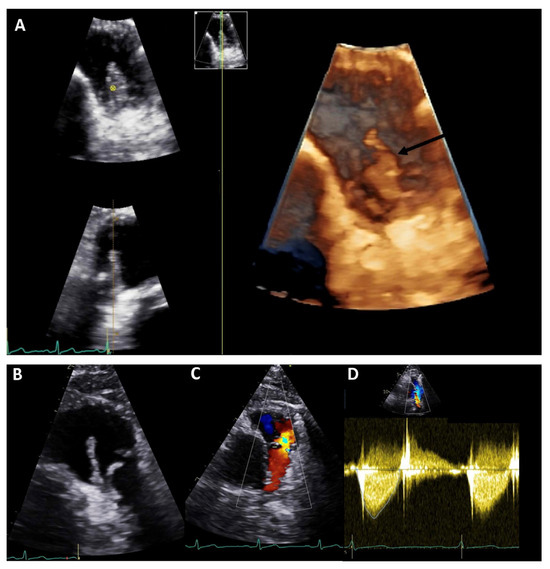

Figure 1. Transthoracic echocardiography of an adult patient with previous Ross procedure for bicuspid aortic valve using a pulmonary homograft. There are large mobile vegetations (max ~18 × 7 mm, (A,B), black arrows) on the pulmonary homograft. Severe pulmonary regurgitation (regurgitant jet originating in the main pulmonary artery, vena contracta 8.5 mm, (C)); no significant stenosis (mean gradient 13 mmHg, peak gradient 26 mmHg, (D)). The findings are consistent with infective endocarditis. Images courtesy of Ms Joane Daradar—Echocardiography Department, Royal Brompton and Harefield Hospitals, London.